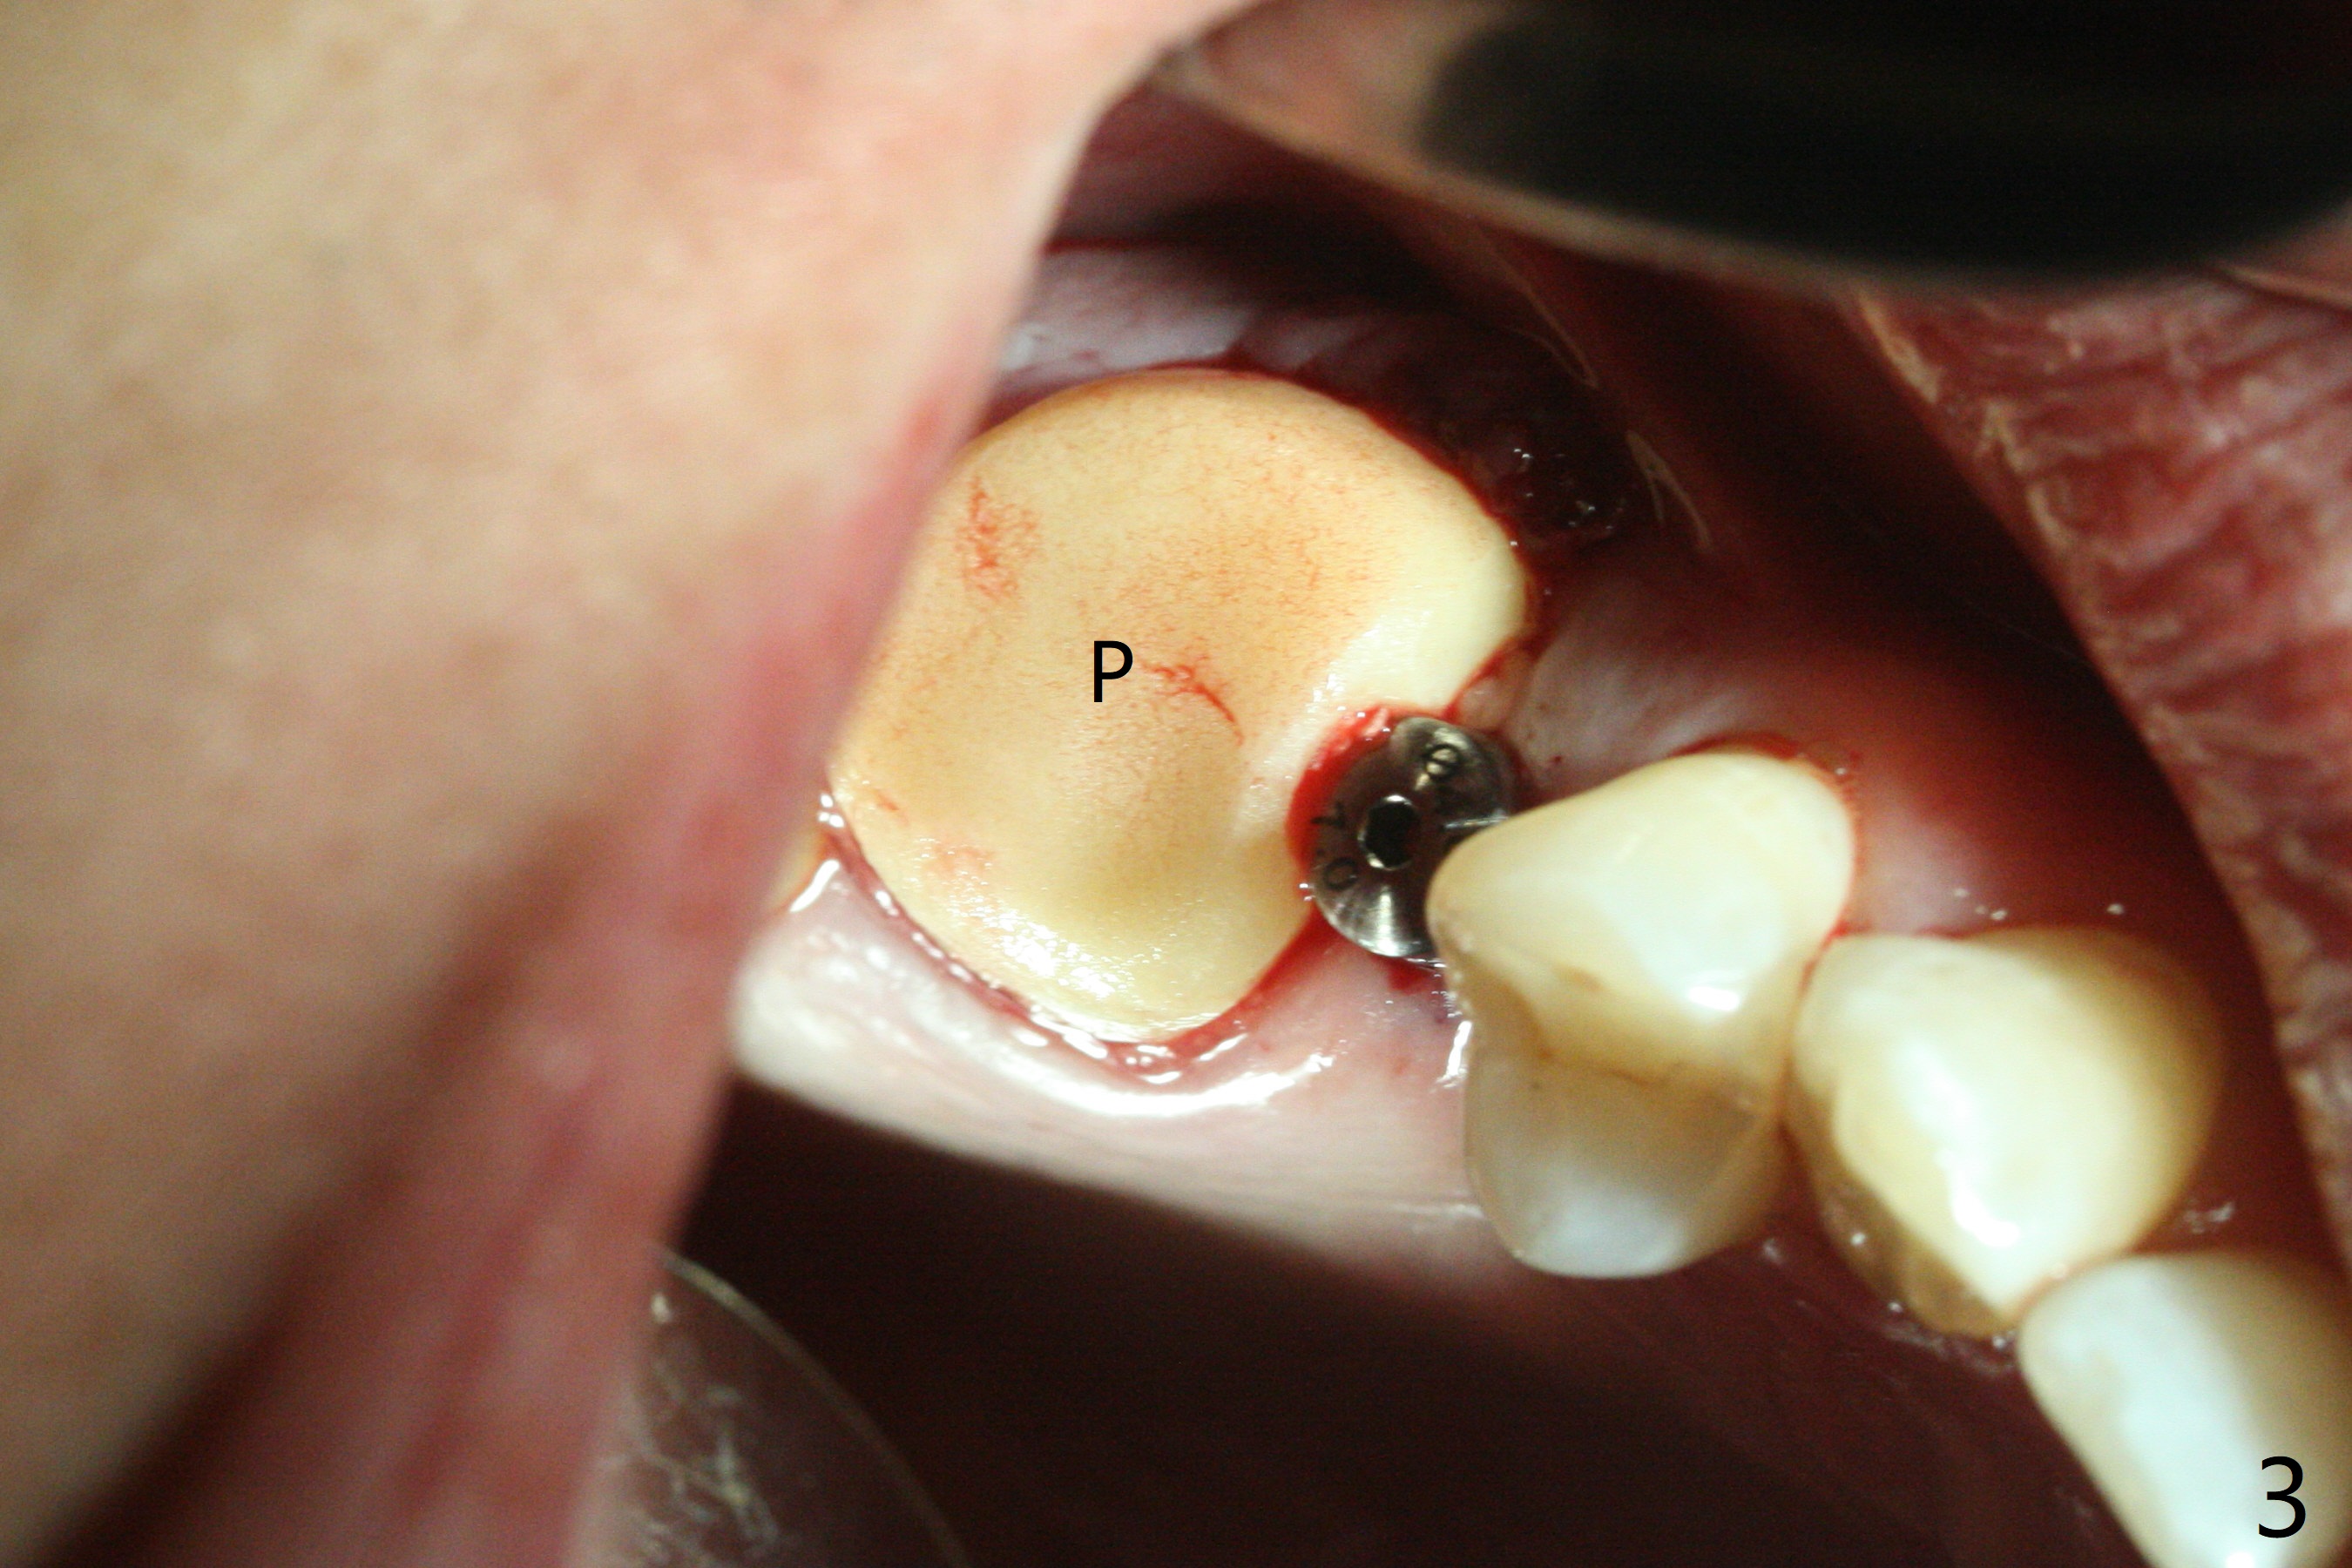

When the tooth #3 with severe buccal gingival recession is extracted and implants are placed at #3 and 4 with guide, sticky bone in 2 large pieces is packed between these implants with a previously large defect in a seemingly secure manner (Fig.1 *). Use of a longer implant at #3 (11.5 mm vs. 10 mm) will reduce the chance of abutment screw loosening in the future. With 2 pieces of PRF membrane coverage, an immediate provisional is fabricated for graft retention (Fig.2,3 P). To stabilize a buccal flap (Fig.2 *, used to be buccal furca gingiva), periodontal dressing is applied later. The buccal socket heals 12 days postop (Fig.4). Apparently new bone forms between the implants 4 months postop (Fig.5). The abutment at #3 may not be completely seated. In fact it is loose, probably related to buccal gingival and gingival cuff erythema 6.5 months postop (Fig.6). Large healing abutments are placed to form the interdental (interimplant) papilla without effect (*). Provisional crowns will be fabricated for the papilla formation. When cemented abutments are placed (Fig.7), papilla formation by manipulation of provisional crowns seems unlikely. Impression is taken. Although there is no implant thread exposure, the buccal plate is concave 7.5 months postop (Fig.8). With special crown design, food impaction should be minimal post cementation (Fig.9,10). There is no bone loss 5.5 months post cementation (Fig.11), while the soft tissue is healthy (data not shown).